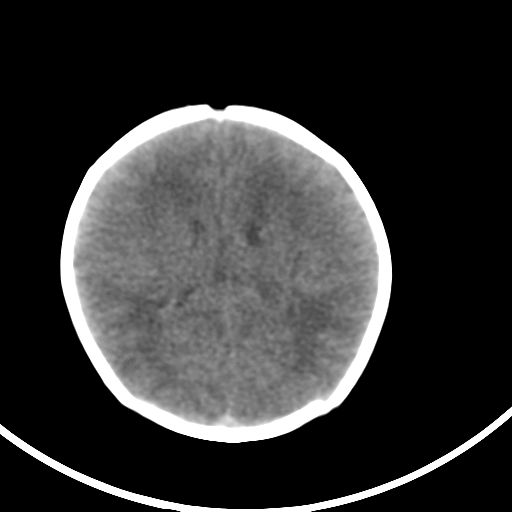

新生儿3天,超过预产期5天剖宫产,有缺氧病史,具体评分不详,现反应差,肌张力低,前囟平,原始反射存在,无苦闹等。

正常

颅底骨质影,正常颅脑表现。

颅底骨质影,正常颅脑表现.

正常颅脑表现。

kaolv小脑幕,后纵裂区蛛网膜下腔出血;轻度脑肿胀

支持9楼意见。

未见明显异常

矢状窦旁征——支持蛛网膜下腔出血

颅脑ct平扫未见异常。

新生儿正常颅内表现

sah。